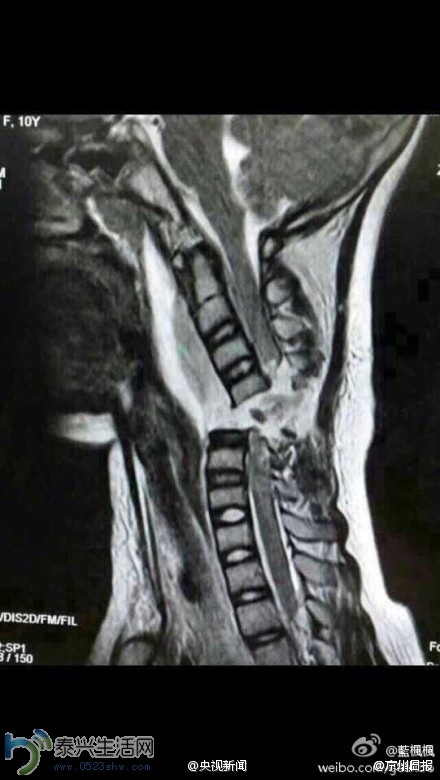

消息是这么说的:这是一位10岁女孩颈椎完全断裂的图片。昨晚她被送至医院救治,损伤原因竟然是坐妈妈的电瓶车,女孩的围巾被绞进车轮。天冷了,为保暖但一定要注意安全,有了安全才有一切!为了小朋友安全必须转起……

当地专家们说,小青的颈椎已经完全断裂,这意味着小青很可能会高位截瘫。在当地北医三院骨科教授的帮助下,小青当天就接受了手术。虽然手术进行得很顺利,但由于脊柱断裂,小青的全身已瘫痪。同时,意外还影响到了肌肉,小青已经不能自主呼吸,目前只能通过呼吸机辅助呼吸。